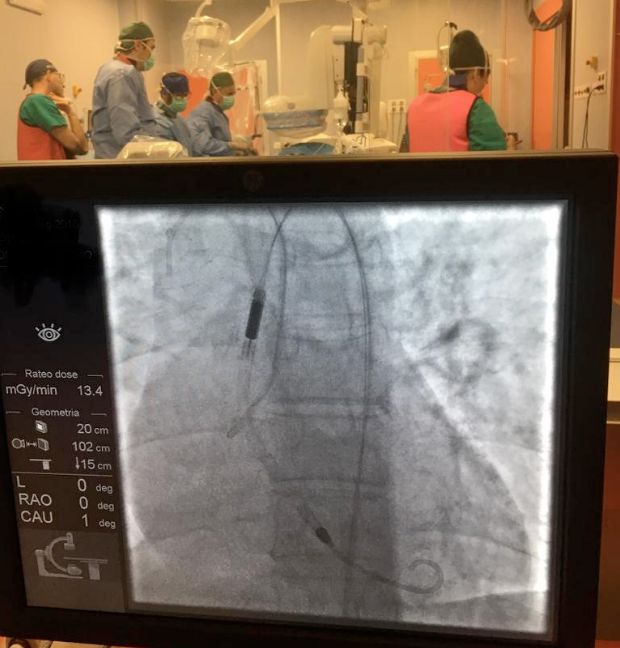

COSENZA L’equipe di Cardiologia interventistica dell’ospedale Annunziata di Cosenza – composta dai dottori Greco, Battista, Caporale, Chiappetta, Leone – ha impiegato per la prima volta il nuovo sistema di supporto alla circolazione cardiaca, poco invasivo e dalle elevate prestazioni, alternativo alla circolazione extracorporea. Si tratta di una “micro pompa” – si legge in una nota dell’Azienda ospedaliera cosentina – inserita in un catetere di soli 4,6 mm di diametro che, attraverso l’arteria femorale, raggiunge il cuore e consente un supporto emodinamico di oltre 3,5 litri al minuto. «Il sistema Impella – si legge ancora nella nota – ha consentito di eseguire una angioplastica coronarica ad altissimo rischio sul Tronco Comune, ultimo vaso coronarico funzionante e severamente stenotico. Il paziente di 50 anni, ricoverato in neurochirurgia per emorragia cerebrale, colto da infarto miocardico acuto con una severa disfunzione del ventricolo sinistro sarebbe stato viceversa non operabile chirurgicamente per le sue coesistenti patologie (recente emorragia cerebrale e malattia oncologica avanzata) e non approcciabile con angioplastica convenzionale senza impiego di questo dispositivo di supporto al circolo che è in grado di sostituirsi completamente all’azione di pompa cardiaca, garantendo il flusso sanguigno a tutto l’organismo, durante l’intervento».

L’inserimento del dispositivo è stato effettuato con il supporto dell’equipe di Chirurgia vascolare e la procedura di angioplastica del Tronco Comune, effettuata in sola anestesia locale, ha avuto «completo successo», con miglioramento della funzionalità cardiaca e stabilizzazione del quadro clinico ed emodinamico. Il paziente si è mobilizzato dopo 24 ore ed è stato dimesso dopo sei giorni.